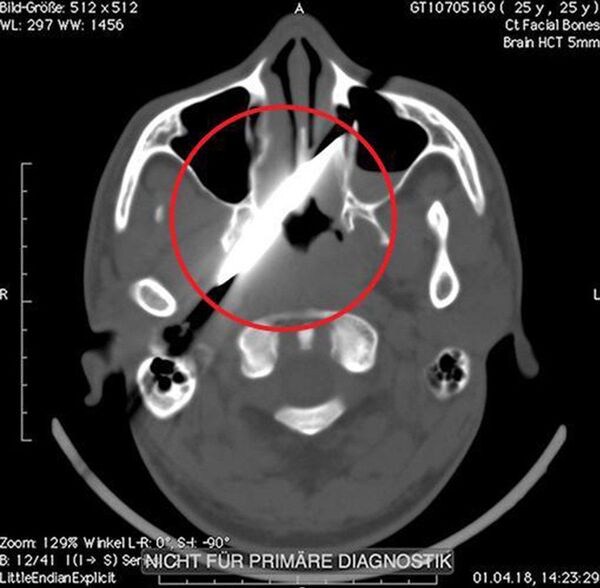

Os exames mostram a lâmina dentro da cabeça do homem, logo atrás do nariz. O sul-africano, de 25 anos de idade, foi ao hospital na manhã de domingo por sofrer um ferimento na noite anterior após ajudar seu amigo em uma briga.

Como é possível ver no Raio-X, a faca penetrou profundamente sua cabeça. Os médicos explicaram que o homem sobreviveu devido ao fato de a faca não ter atingido artérias importantes. Além disso, o homem passou quatro dias com o objeto no crânio devido à burocracia, após esse período, o homem conseguiu passar pela operação.